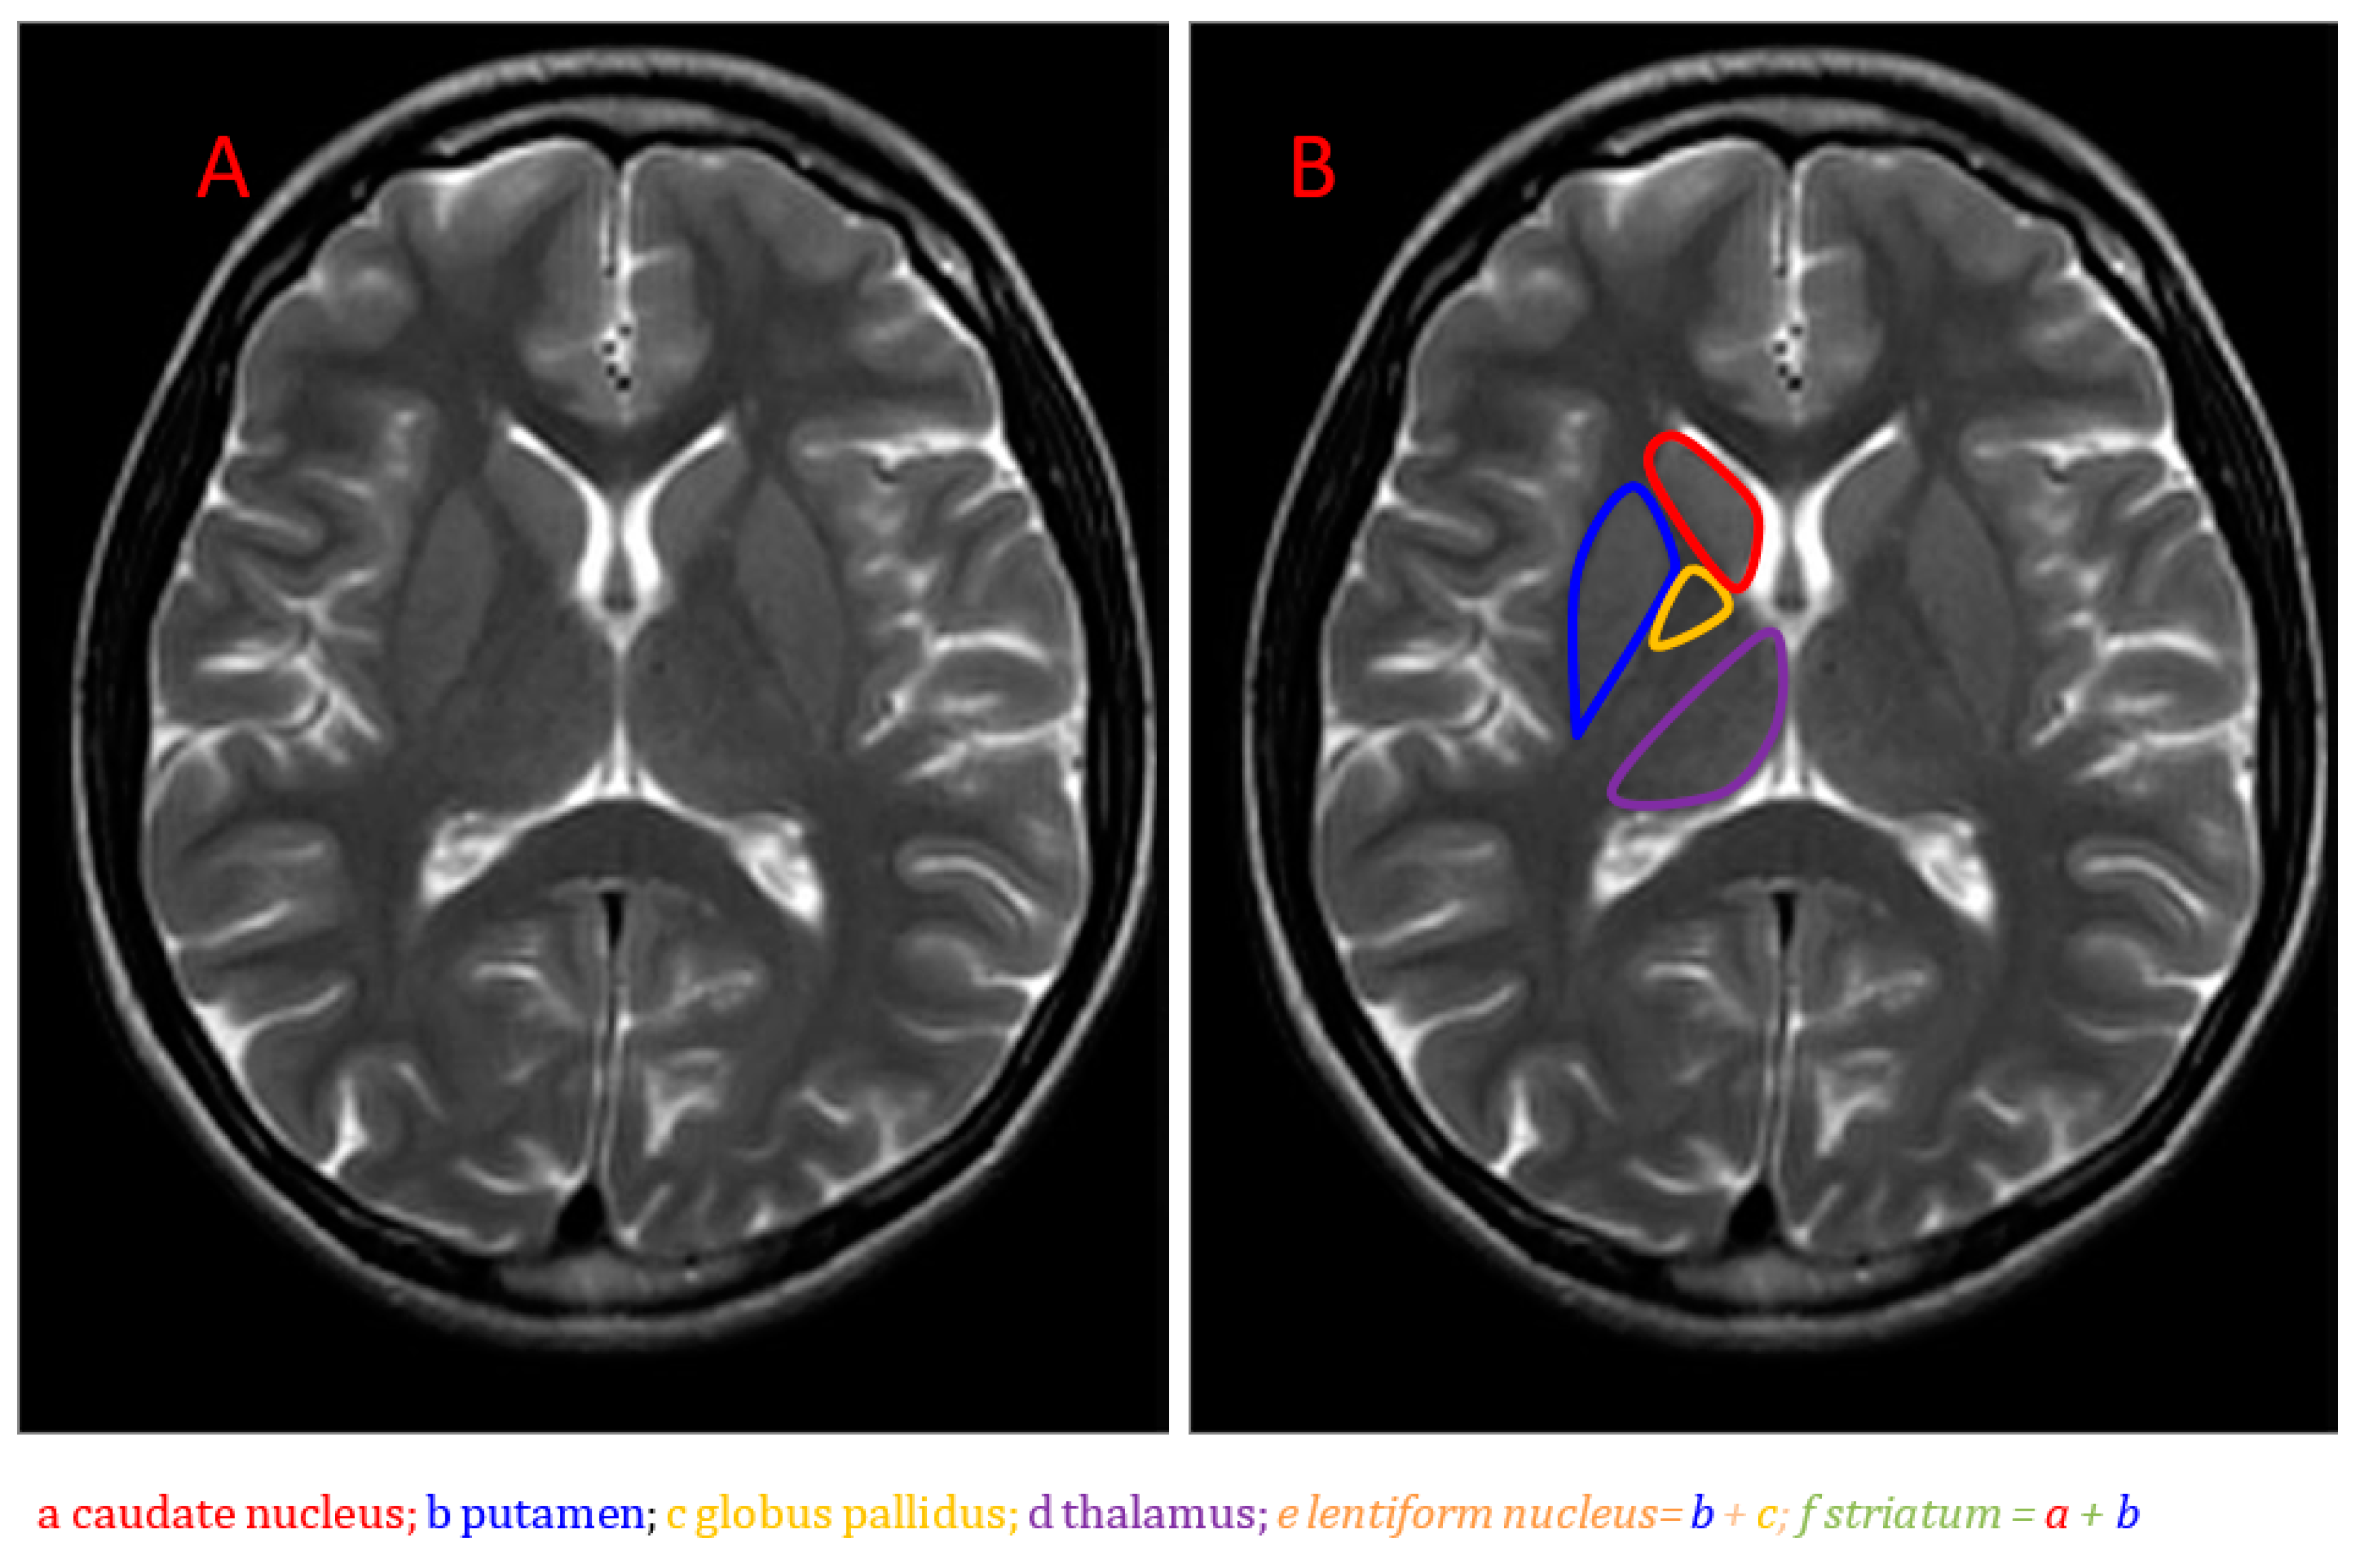

An Introduction to Neurometabolic Disease